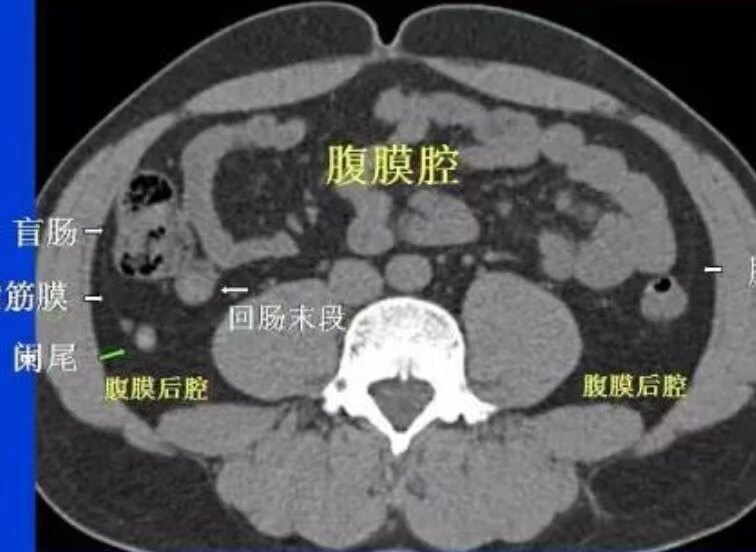

“小小”闌尾炎不簡單

闌尾炎,在大部分老百姓心里都是個(gè)“小病”。事實(shí)上大部分的闌尾炎手術(shù)確實(shí)也是個(gè)小手術(shù),尤其在如今腹腔鏡微創(chuàng)手術(shù)普及的年代,常規(guī)的闌尾炎手術(shù)基本上也就是十來二十分鐘的事情。但是總有“小部分”的時(shí)候,下面我就從醫(yī)生的角度給大家聊一聊這些你可能不知道的事。首先說闌尾炎的診斷,在腹部CT沒有普及的年代,闌尾炎是右下腹痛最容易被大家診斷的疾病,但您有可能不知道闌尾炎也是胃腸外科誤診率高居首位的疾病。每年醫(yī)院都會接診大量的被誤診為闌尾炎的病人,包括宮外孕、盆腔炎、膀胱炎、子宮穿孔、消化道穿孔等等,屢見不鮮。即使如今腹部CT已經(jīng)廣泛用于闌尾炎的診斷,但有些不典型的闌尾炎還是容易漏診,同時(shí)一些其它少見疾病如回盲部結(jié)核、克隆恩病,甚至回盲部腫瘤等如果有闌尾炎一樣的臨床和影像表現(xiàn)也極易誤診。要知道腹部CT在整個(gè)腹腔尋找闌尾也是那僅僅幾個(gè)層面,有時(shí)候如果闌尾炎炎癥不嚴(yán)重,水腫不明顯,或者位置有異常,固定的已經(jīng)打印出的CT片還真看不容易看到,還需要在電腦上打開一幀一幀地順著腸管往下追蹤尋找才能看見(下圖是我在網(wǎng)上下載的兩張照片,供大家參考)。所以診斷闌尾炎絕對是個(gè)技術(shù)活,如果您碰到一個(gè)胃腸大夫考慮您是闌尾炎,但還是不厭其煩問您病史,反復(fù)地摸和按您的肚子,反復(fù)地去看CT片,甚至說我去電腦上看看片子,他還真不一定是您想的那樣“一個(gè)闌尾炎,小題大做”,很有可能是他見過太多太多誤診的病例,剛好您又是不太典型的闌尾炎,所以他是小心小心又小心。咱們再說闌尾炎的治療,不管是開刀還是腔鏡手術(shù),大部分確實(shí)是大家印象中的“小手術(shù)”。但總有麻煩的時(shí)候,闌尾隨著發(fā)病時(shí)間的延長,周圍炎癥會越來越重,所以會穿孔,形成膿腫,也會被周圍腸管組織包裹形成致密的粘連。這個(gè)時(shí)候切除闌尾就不是您想的那樣簡單了,會碰到各種各樣的問題(如下圖所示的幾張圖片)。所以闌尾炎發(fā)病超過72小時(shí),經(jīng)常會遇到大夫和您建議保守治療,等炎癥消退了再手術(shù)。但也會存在保守治療無效,膿腫加劇或者膿腫播散,或者炎癥導(dǎo)致腸粘連梗阻,這個(gè)時(shí)候手術(shù)的目的是進(jìn)去做膿腫引流,分離粘連,而闌尾切不切是其次,闌尾可能會“爛掉”找不見,也可能會因?yàn)檎尺B嚴(yán)重分不開切不掉。如果這個(gè)時(shí)候大夫還捎帶給您把闌尾切掉了,您又順利出院了,那恭喜您碰到一位水平高又為您著想的好大夫,但同時(shí)您也可能不知道在您恢復(fù)的過程中他可能每天都戰(zhàn)戰(zhàn)兢兢時(shí)刻關(guān)注著您有沒有腸漏、梗阻、腹腔殘留感染等并發(fā)癥。作為工作多年的胃腸大夫,見過太多太多的專家,主任都栽到闌尾的診斷和治療這個(gè)“坑”里后悔不已,因?yàn)榇蠹叶加X得闌尾是個(gè)小病,闌尾手術(shù)是個(gè)小手術(shù),不理解。所以大家還是要認(rèn)真對待闌尾炎,去正規(guī)的醫(yī)院及時(shí)診治,千萬不要掉以輕心,因?yàn)檎l也不敢保證自己會落到那個(gè)令醫(yī)生也頭痛的“小部分”里。